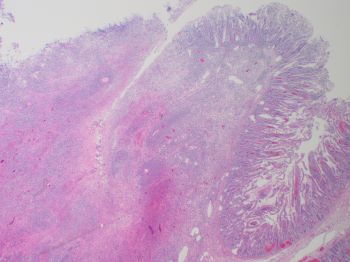

On H&E, the cytologic features of the neoplastic T-cells are typical of MEITL rather than EATL, showing greater uniformity in appearance than would be seen in EATL. Typical for MEITL, the T-cells in this case are mostly medium-sized, contain relatively round nuclei, and have inconspicuous nucleoli. In EATL, tumor cells show pleomorphism, widely varying in cytologic appearance with medium or large sized cells containing round or angulated nuclei with prominent nucleoli.